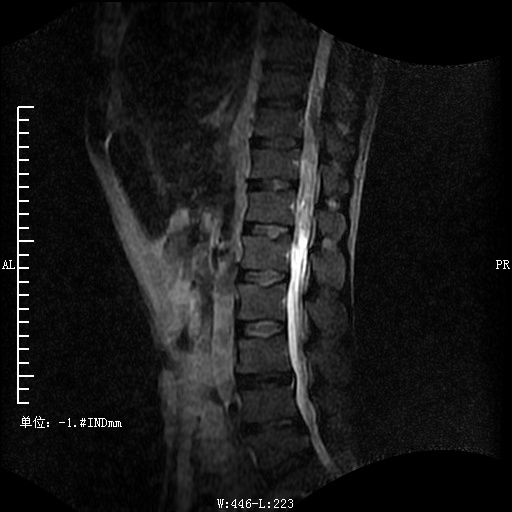

病史:患者中年男性;起病缓,病程长;以"腰背疼痛4年伴双下肢麻木无力进行性加重1年。"为主要表现,查体:查体:神清,腰背部:胸椎10-骶椎皮肤可见"艾交"瘢痕,椎体棘突广泛压痛,腹壁反射存在,腹股沟平面以下可见深浅感觉明显减退,以右侧为甚,疼痛刺激明显降低,肌力Ⅲ级,肌张力不高,病理征阴性,鞍区感觉降低,提睾反射存在;我院MRI示:1.腰椎退变;2.腰椎多个椎体许莫结节形成;3.胸10-腰1椎管内硬脊膜下见梭形片团状混杂稍长T1和稍长T2信号,脊髓向右推及变细,肿瘤性病变?其他?完善术前检查于全麻下经后路椎管内病变切除术+椎管降压术+后路内固定,术后予抗感染,止血,营养神经,请康复科康复训练,经治疗后患者现生命体征平稳,切口愈合I/甲,未见溢液及脑脊液漏,双下肢肌力左侧3-级,右侧肌力3+级,肌张力不高,感觉左侧下降至膝关节平面,右侧踝关节平面,术后3月复查患者扶拐行走。

术后脊椎: